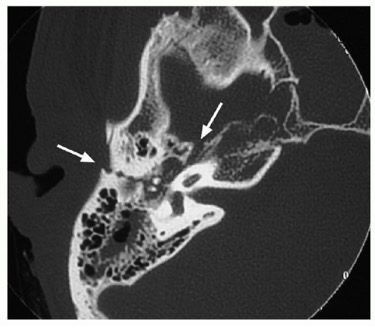

④ 신경성 난청 – 8번 신경 및 측두골 골절

제8뇌신경(청신경)은 단단한 측두골에 둘러싸여 있어 보호를 받지만, 측두골 골절이나 내이도(IAC)와 뇌 사이의 신경 견인·압박 등에 의해 손상될 수 있습니다. 이 경우. 청력 저하와 더불어 심한 회전성 어지럼, 안진, 안면신경 마비가 동반되기도 하며, 영상 검사(측두골 CT, 내이 MRI)를 통해 골절·신경 압박 여부를 확인할 수 있습니다.

영상 검사

-측두골 CT: 골절, 중이 내 혈액, 이소골 상태